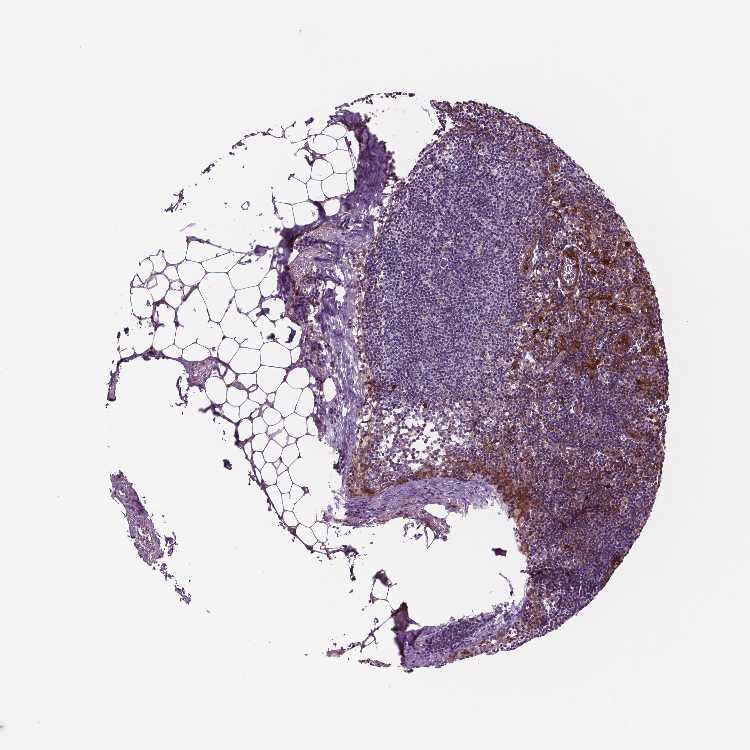

TISSUE PRIMARY DATA LYMPH NODE Show tissue menu

Lymph node

LYMPH NODE - Expression summary

LYMPH NODE - Antibody stainingi

Antibody staining in the annotated cell types in the current human tissue is reported as not detected, low, medium, or high, based on conventional immunohistochemistry profiling in selected tissues. This score is based on the combination of the staining intensity and fraction of stained cells.

Each image is clickable and will lead to virtual microscopy that enables deeper exploration of all samples and also displays staining intensity scores, fraction scores and subcellular localization as well as patient and tissue information for each sample.

Antibody CAB015336Antibody CAB069404

Germinal center cells MediumMedium

Non-germinal center cells LowMedium